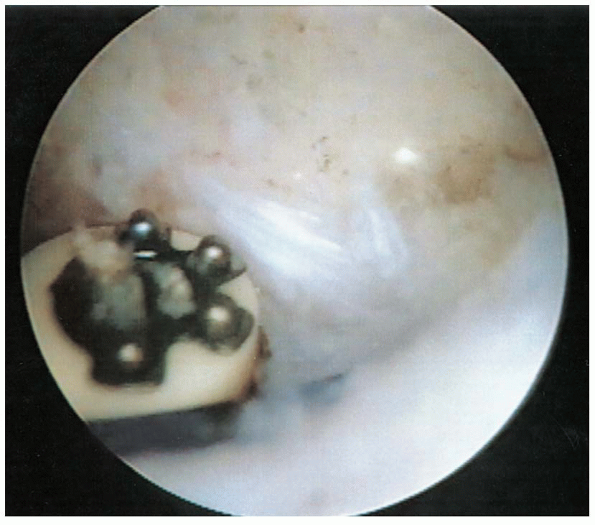

![]() |

|

FIGURE 2-12. Rotator cuff tear with the PDS suture marker as viewed arthroscopically on the bursal side of the tear.

FIGURE 2-13. Release of the coracoacromial ligament using a radiofrequency device.